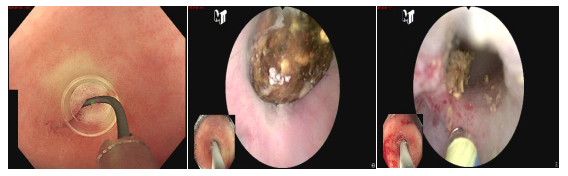

"液電碎石"巧解難題——內(nèi)鏡微創(chuàng)治愈闌尾巨大結(jié)石合并慢性闌尾炎

患者闌尾巨大結(jié)石合并慢性闌尾炎,因闌尾口嚴(yán)重粘連操作極具挑戰(zhàn)。團(tuán)隊(duì)?wèi){借嫻熟技術(shù),在導(dǎo)絲精準(zhǔn)引導(dǎo)下,成功實(shí)施內(nèi)鏡下"液電碎石",取出結(jié)石并徹底沖洗,手術(shù)一氣呵成,展現(xiàn)了內(nèi)鏡微創(chuàng)治療復(fù)雜闌尾病變的技術(shù)優(yōu)勢(shì)。